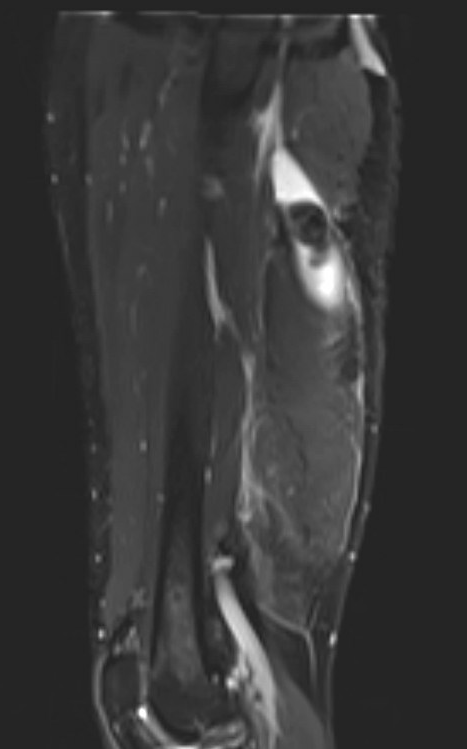

MRI

Incomplete tears

High grade partial tear proximal hamstring

High grade partial tear proximal hamstring